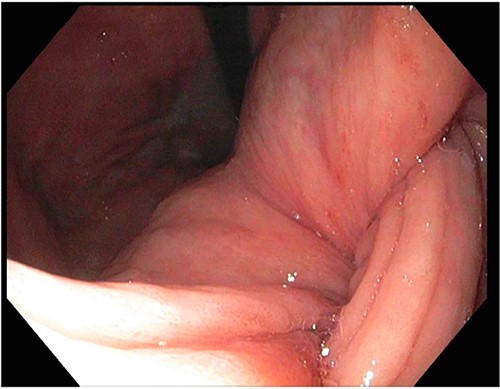

A 72-year-old patient with no past surgical history and a past medical history of developmental delay, hypertension and hyperlipidemia presented to the Emergency Department in mild distress with periumbilical abdominal pain, nausea and intractable vomiting for 1 day. The patient denied any hematemesis, bowel changes, fever, melena or hematochezia. On physical exam, the abdomen was unremarkable, and a computed tomography (CT) scan with contrast of abdomen and pelvis revealed a 5.6 × 5.3 cm heterogeneous mass arising from the body of the stomach extending into pylorus with no evidence of bowel obstruction and liver metastasis (Fig. 1). Subsequently, esophagogastroduodenoscopy (EGD) showed a large, fungating and ulcerated mass and it was reported to involve two-thirds of the luminal circumference in the gastric body (Fig. 2). Cold forceps biopsy showed gastric mucosa with hyperplastic changes, mild chronic active antral gastritis with focal intestinal metaplasia, negative for Helicobacter Pylori and dysplasia. Surgical management was discussed with the family, but they refused any surgical intervention.

A large fungating gastric mass arising from the body of the stomach on endoscopy.